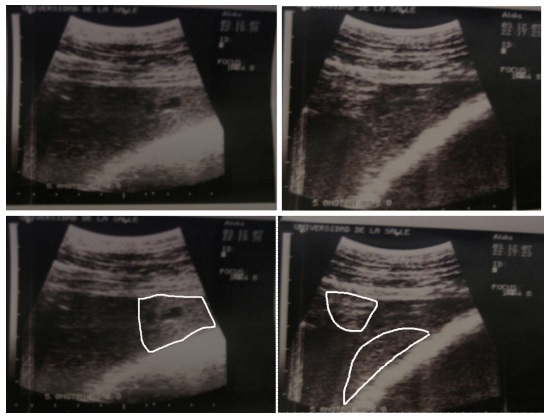

La ultrasonografía (Figura 2) reveló fo- cos de hiperecogenecidad en el pulmón, compatible con bronconeumonía abscedativa.

Figura 2 Vaca Holstein de 8 años. Izquierda: Se observa foco de consolidación pulmonar en porción superior izquierda (imagen dentro de la forma blanca de carácter hiperecoico) con un aro anecoico que puede ser un bronquio; Derecha: Focos de consolidación pulmonar en porción superior izquierda (imágenes hiperecoicas dentro de las formas blancas), congruente con neumonía supurativa.

La ultrasonografía reveló focos hiperecoicos compatibles con consolidación y bron co-neumonía supurativa crónica. Al escanear los pulmones, se pueden evidenciar múltiples abscesos, pero no se evidencian efusiones pleurales, aunque algunas áreas subpleurales hipoecogénicas pueden indicar una hemorra gia pulmonar (Tharwat, 2010). En este caso no se alcanzó a evidenciar el hígado y la vena cava por medio de ultrasonografía, aunque esta técnica es muy útil para el diagnóstico de abscesos hepáticos (Braun, 2005). En el presente caso, mientras el paciente estaba hospitalizado se realizó el diagnóstico confirmativo de bronconeumonía supurativa y un presuntivo de TVCC por la anamnesis y examen clínico, siendo este último confirma- do en la necropsia (Figuras 3 y 4).